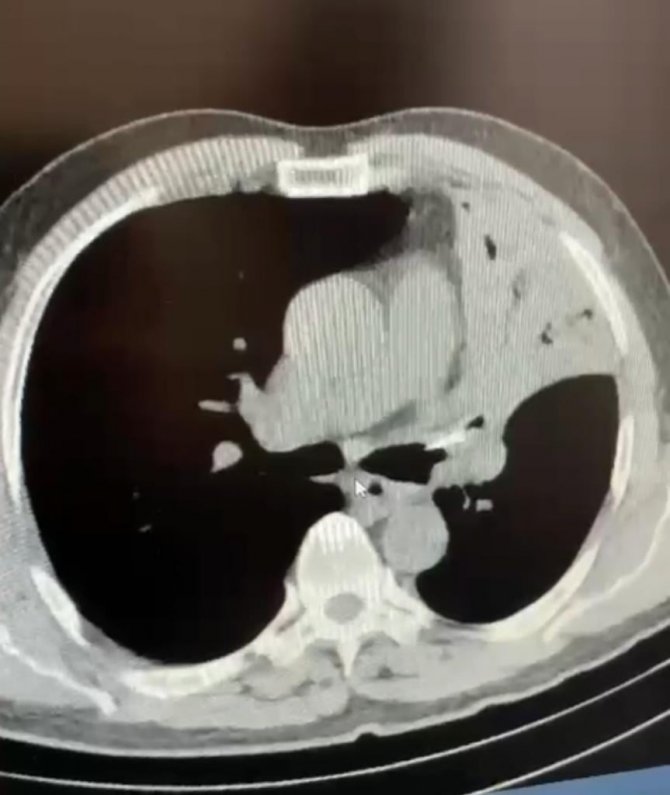

Bolu'da öksürük ve şiddetli ağrı şikayetiyle gittiği hastanede 5 yıldır sol akciğerine saplanan lades kemiğiyle yaşadığını öğrenen Mehmet Salih Fer, kemiğin ameliyatla alınması sonucu sağlığına kavuştu.

Edinilen bilgiye göre, Düzce'nin Cumayeri ilçesinde yaşayan Mehmet Salih Fer, uzun süredir devam eden öksürük ve şiddetli ağrı şikayetiyle AİBÜ İzzet Baysal Eğitim ve Araştırma Hastanesi'ne gitti. Fer'in yapılan muayenesinde sol akciğerine lades kemiği saplandığı tespit edildi. Fer'in 5 yıl boyunca akciğerinde saplanmış halde bulunan lades kemiği yapılan ameliyatla alındı. Sağlığına kavuşan Fer, yapılan son kontrollerinin ardından taburcu edildi.

5 yıl boyunca öksürük, şiddetli ağrı sırtında yanma şikayetleri bulunduğunu ifade eden Mehmet Salih Fer, "Aynı şikayetlerle hastanelere gittim, muayenelerim yapıldı, filmler çekildi. Sık sık enfeksiyon geçiriyordum, farklı farklı tanılar konuldu ve ilaç tedavileri başlatıldı. Ancak hiçbir sonuç alamadım ve şikayetlerim devam etti. Son olarak İzzet Baysal Eğitim ve Araştırma Hastanesi Göğüs Cerrahisi kliniğine geldim. Burada doktorlarım tarafından muayenelerim ve tetkik işlemlerim yapıldı. Neticede sol akciğerimde yaklaşık 5 senedir bir lades kemiği ile yaşadığımı öğrendim" dedi.